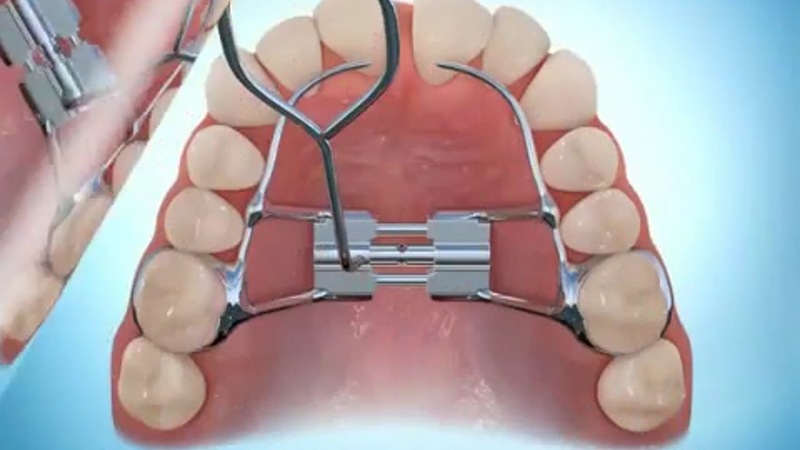

Nong hàm là cách sử dụng các khí cụ để nới rộng vòm họng, giúp khung hàm cân đối hơn và đủ chỗ cho răng di chuyển cũng như đạt hiệu quả thẩm mỹ sau khi niềng răng. Mỗi bệnh nhân sẽ được thiết kế khí cụ nong hàm riêng phù hợp với khuôn hàm của mình. Nong hàm cần được đeo hằng ngày để cung hàm dần dần nới rộng ra từng chút, tạo khoảng trống để răng có thể di chuyển vào mà không cần nhổ răng.

Hiện nay có hai loại khí cụ dùng trong nong hàm là nong hàm tháo lắp và nong hàm cố định: